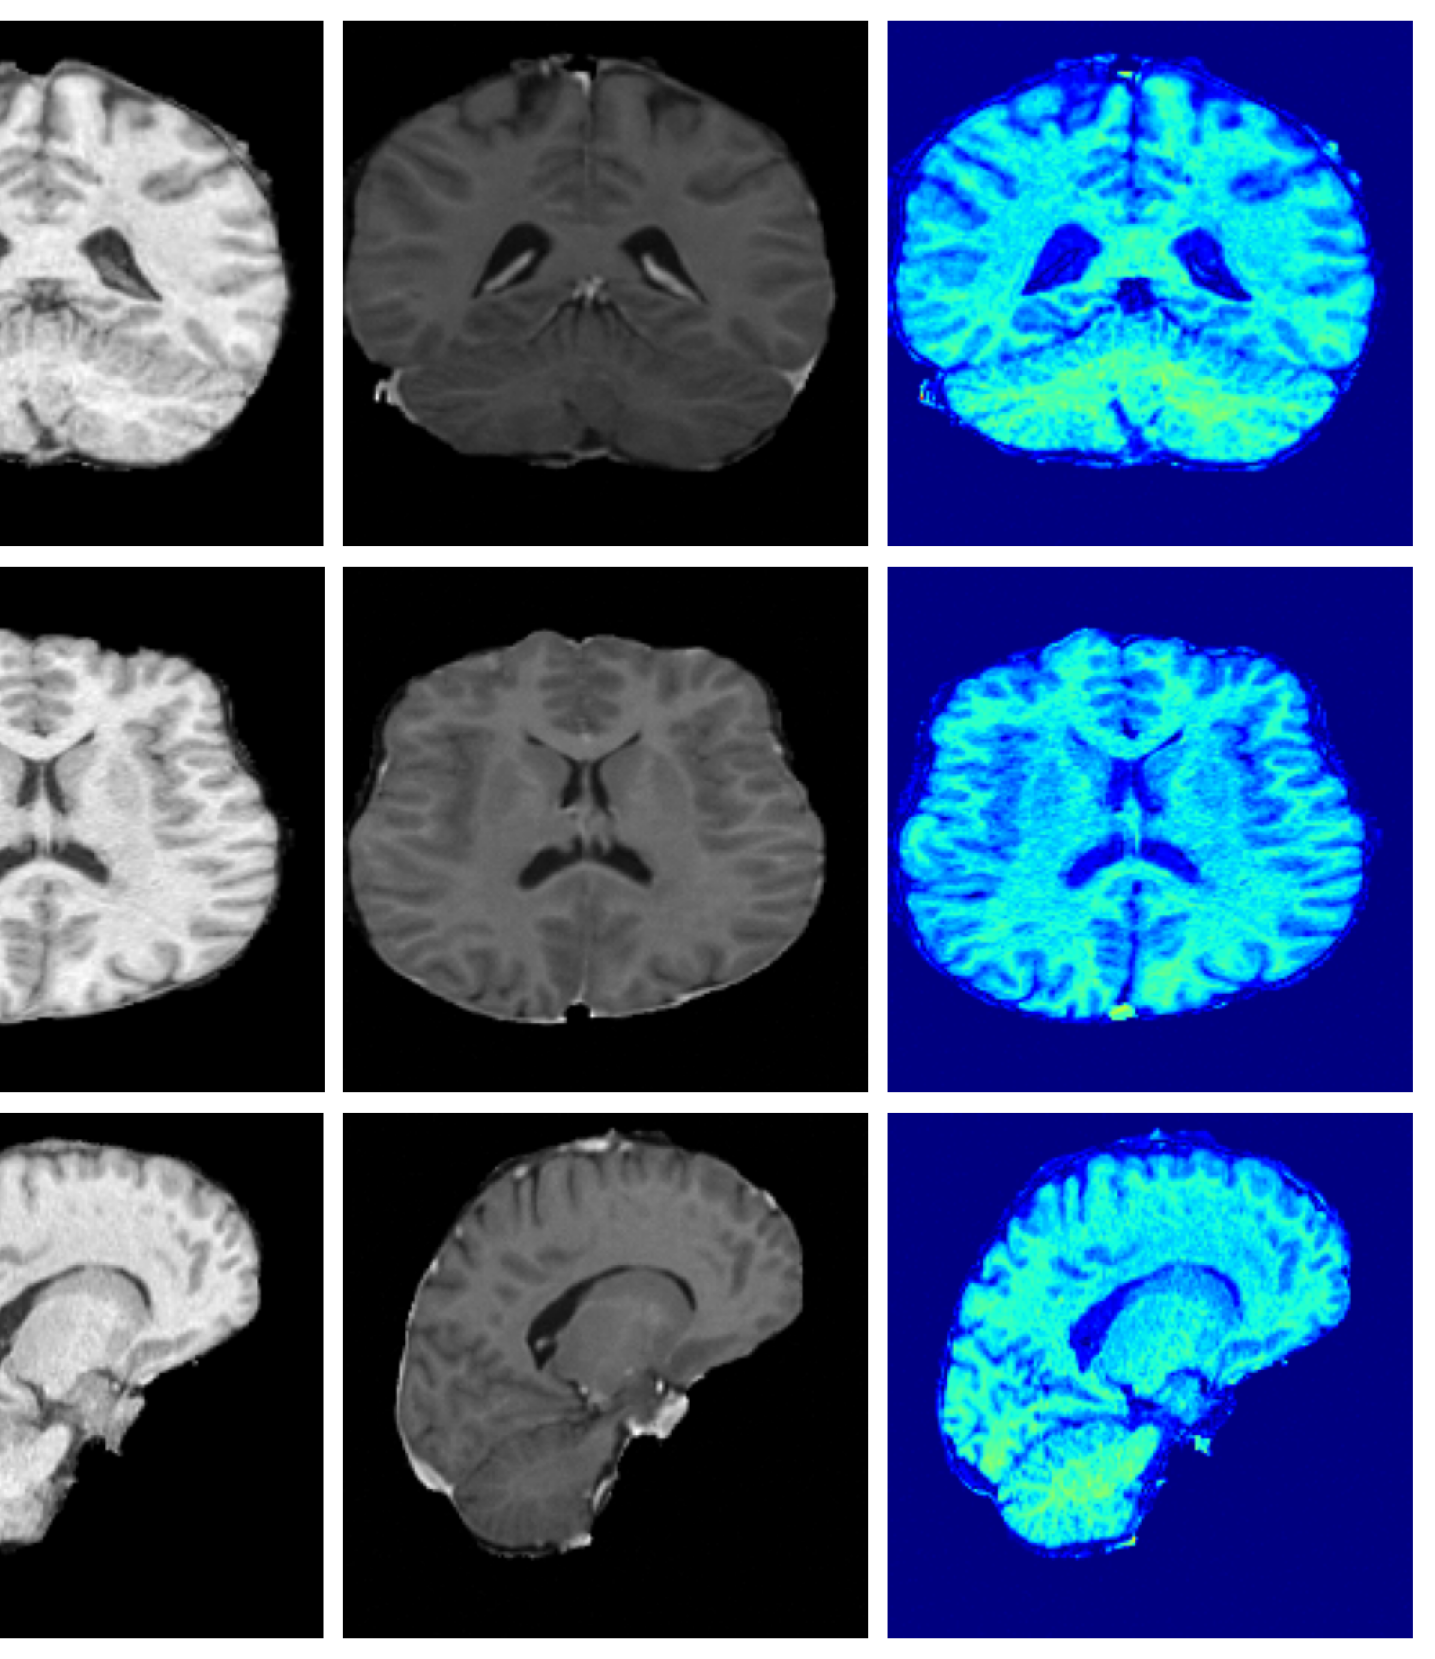

Figure 3 (additional examples in Appendix A.9) shows that SynthSR preserves healthy tissue but struggles with large lesions, while DDPM-2D and DDPM-3D, despite producing high-contrast anomaly maps, generate unrealistic homogeneous inpainting, consistent with their lower performance in Table 3. In contrast, our method yields the most anatomically plausible inpainted regions, although anomaly maps appear subtle due to low contrast between lesions and healthy tissue.

A.9 Additional qualitative inpainting results

Additional qualitative results for the ATLAS and BraTS datasets are given in Figures 12 and 13, respectively.